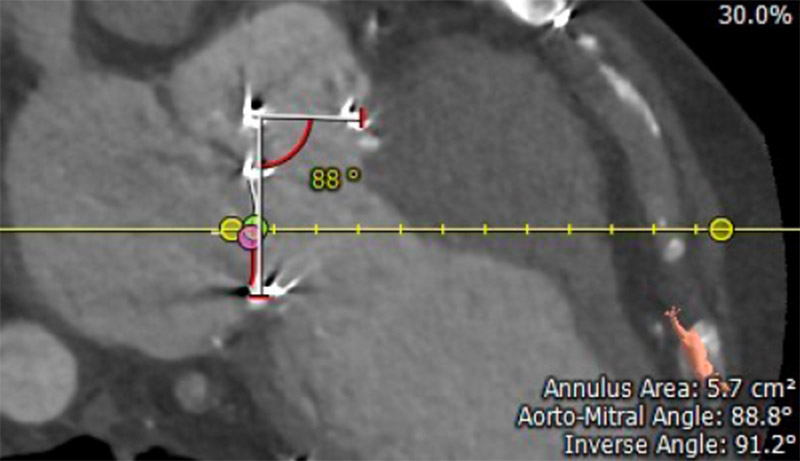

3-D CTA reconstruction of a post-Commando patient

3-D CTA reconstruction of a post-Commando patient, demonstrating the aortomitral angle measurement.

They found that the aortomitral patch length was inversely proportional to the aortomitral angle, with the optimal range between 0.5 cm and 1 cm in length to allow for low coronary obstruction risk and easy re-access. If the patch is too short, it could increase stress on the anatomy and can potentially cause tearing in the valve leaflets, while a patch that is too long can fold in on itself, making access for a future transcatheter procedure challenging.